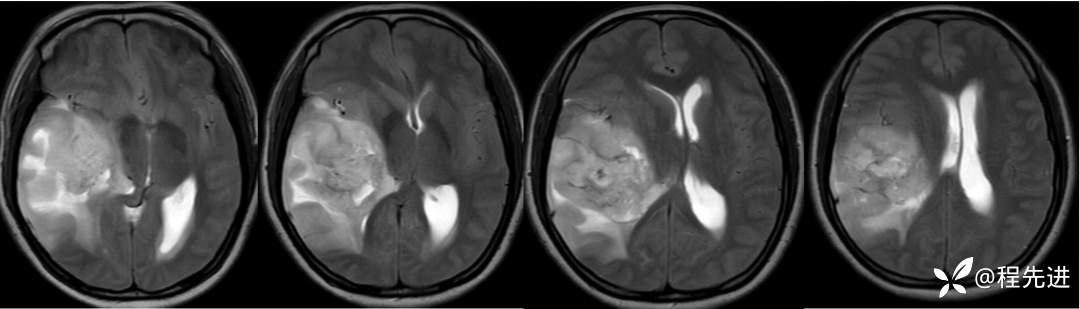

T2: